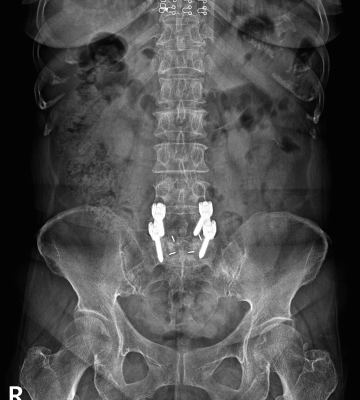

척추전방전위증 수술 전·후

2022.09.21

2022.12.30

ㆍ환자 동의를 받은 자료이며, 이미지 사진은 실물과 다를 수 있습니다.